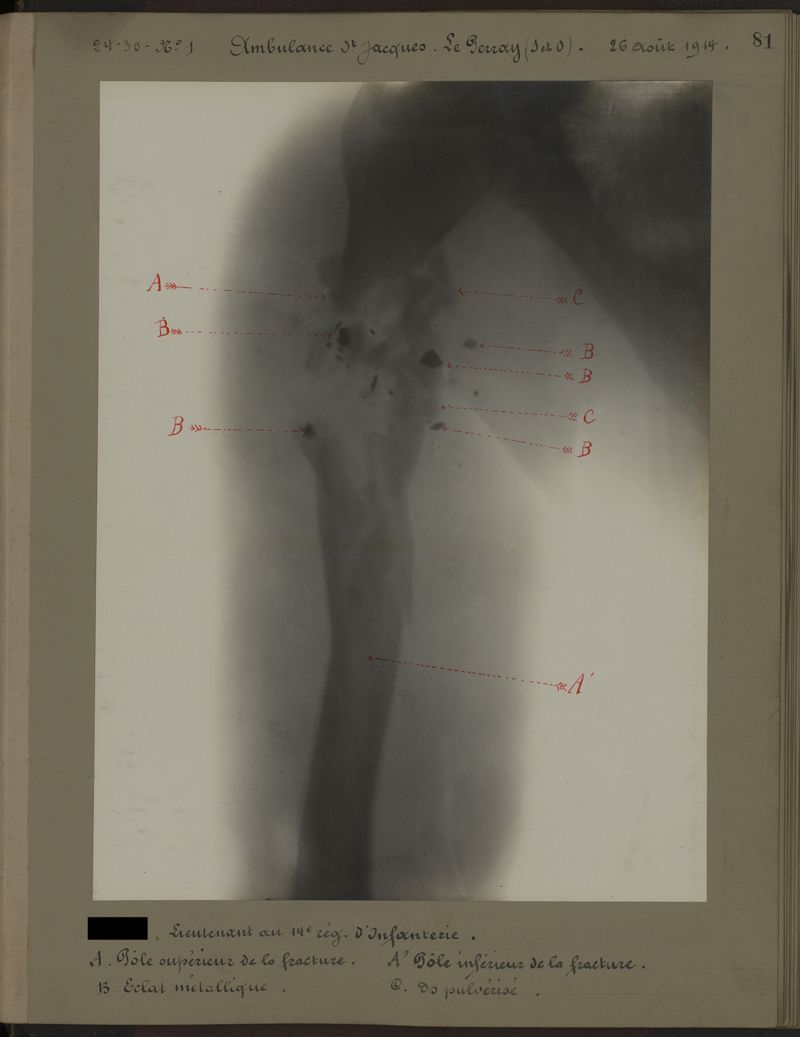

Deux albums de radiographies de la Première Guerre mondiale. Collection du laboratoire central de radiographie de la Salpêtrière. Deuxième album.

1915.